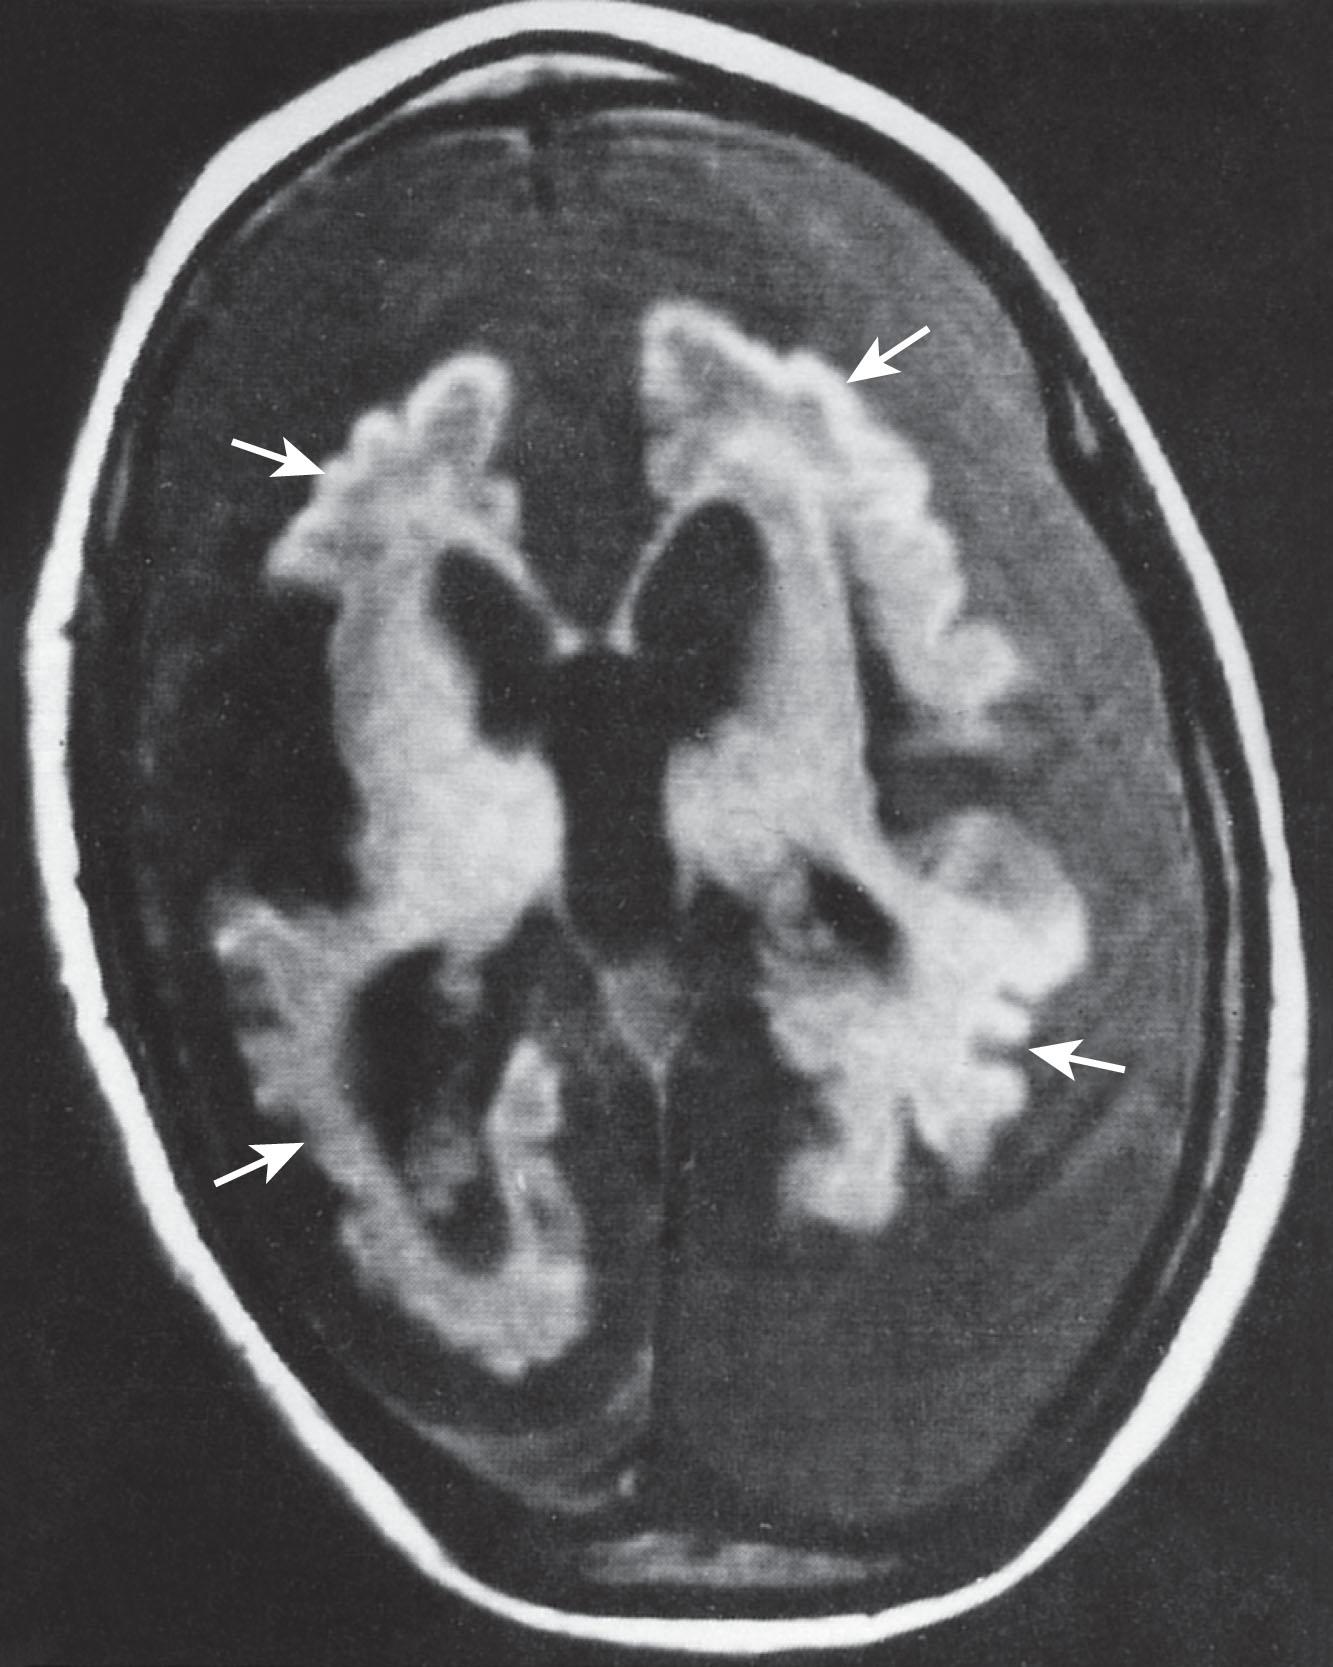

Fig. 33.4, Early infantile neuronal ceroid-lipofuscinosis: MRI scan. This T1-weighted MRI scan, performed at 4 years of age, shows striking cortical atrophy and markedly dilated lateral ventricles, secondary to atrophy. The shriveled cortical surface is marked by arrows ; the low signal intensity surrounding the brain is extracerebral fluid. In congenital neuronal ceroid-lipofuscinosis, the atrophy is present in the first weeks and months of life (see Fig. 33.5 ).